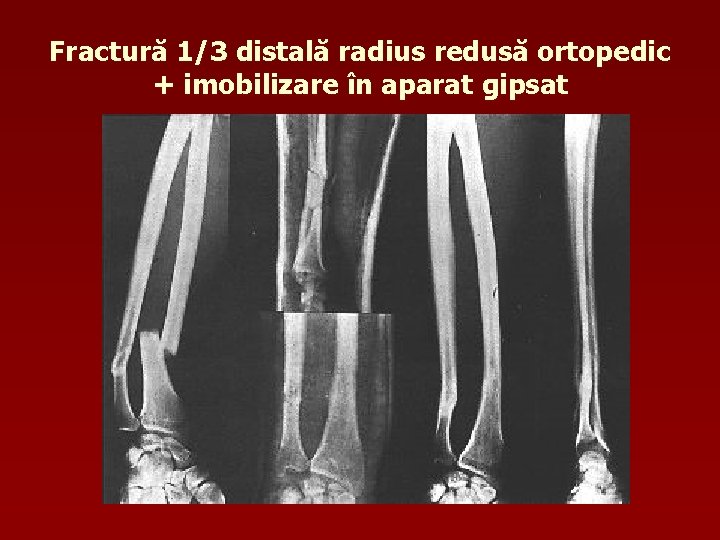

Fractură 1/3 distală radius redusă ortopedic + imobilizare în aparat gipsat